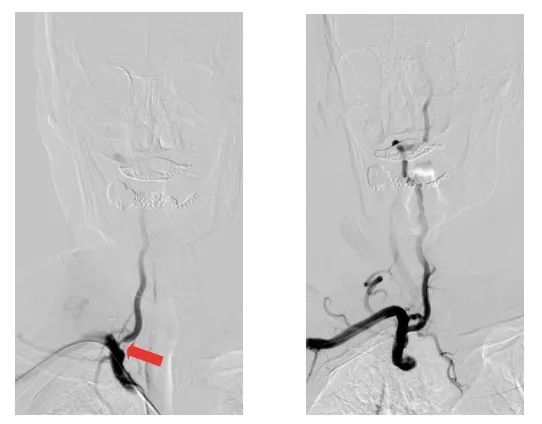

術前術后影像對比(紅色箭頭所指位置為狹窄處)

79歲的劉大爺,因反復頭昏頭暈不適來江陰市人民醫院就診。神經內科副主任醫師陸強彬為其行全腦動脈造影檢查后發現,劉大爺的右側頸內動脈閉塞,右側椎動脈開口處重度狹窄,并向右側頸內動脈代償供血。

醫療團隊僅用時40多分鐘,便通過右側橈動脈入路,成功在患者的椎動脈置入1枚支架。術后,患者的椎動脈狹窄解除,頭暈頭痛癥狀消失,即可下床活動,身體恢復良好。